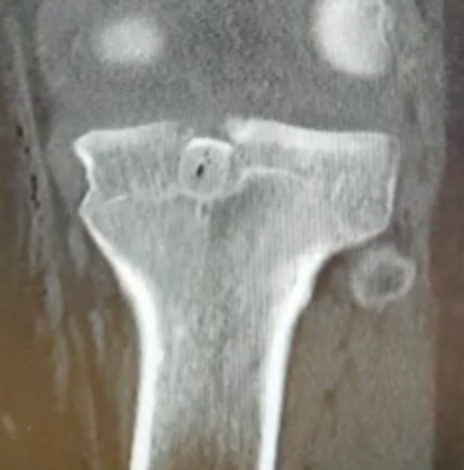

2. Displaced bony avulsion fracture

1. Repair bony avulsion

Repair Bony Avulsion

Arthroscopic

Hooper et al. Am J Sports Med 2018

- systematic review of PCL tibial-sided bony avulsions comparing open and arthroscopic repairs

- 28 articles with 637 patients

- better functional outcomes with arthroscopic repair

- higher risk of stiffness in the arthroscopic group